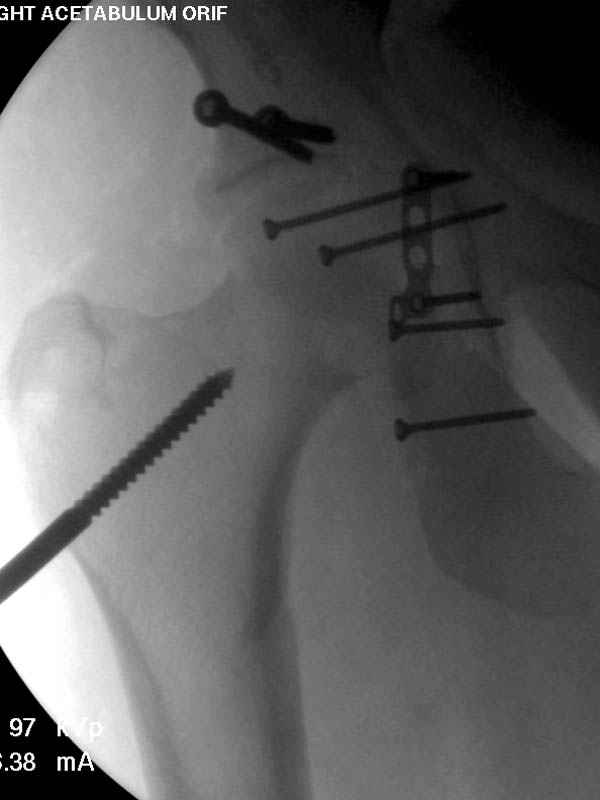

Дополнительно имеется перелом ацетабулума: задняя

колонна с полупоперечным переломом, и переломы костей лица.

На седьмой день зафиксирован перелом ацетабулума через задний доступ. Перед операцией для профилактики DVT, IVC фильтер, также получает Lovenox.

По возможности вышлите снимки, сканы таза до

реконструкции, интраоперационные.

По снимку создается впечатление о высоком поперечном переломе, задней колонны, стенки; почему не пользовались *magic screw*?

Не хотелось отклонятся от основной темы, поэтому здесь краткие ответы..

Латеральное положение облегчает проведение тракции через вертел, за 5 мм стержень за вертел (грузом через тракционное приспособление), на обычном рентгенопрозрачном операционном столе, а для положения на животе, наверное, Judet Table более приемлем, потому что там имеется латеральное тракционное устроиство.

Там множество обычных 2.7 мм шурупов, потом идет фиксация основными пластинами.

Снимки здесь....